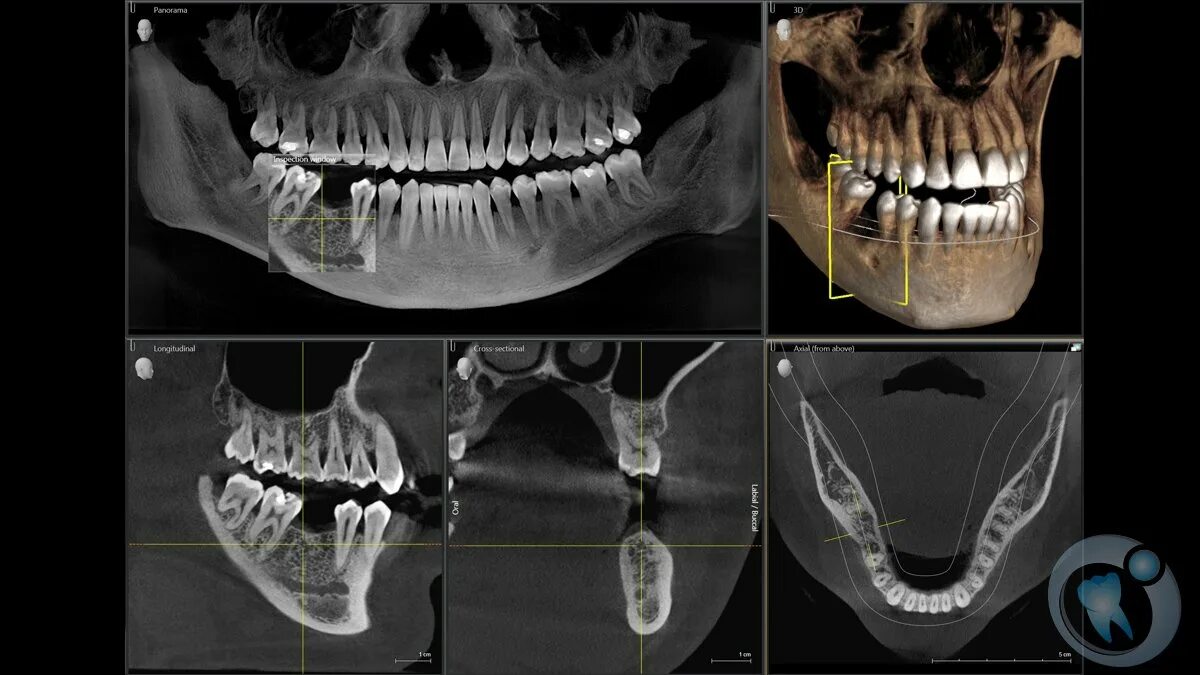

Кл кт